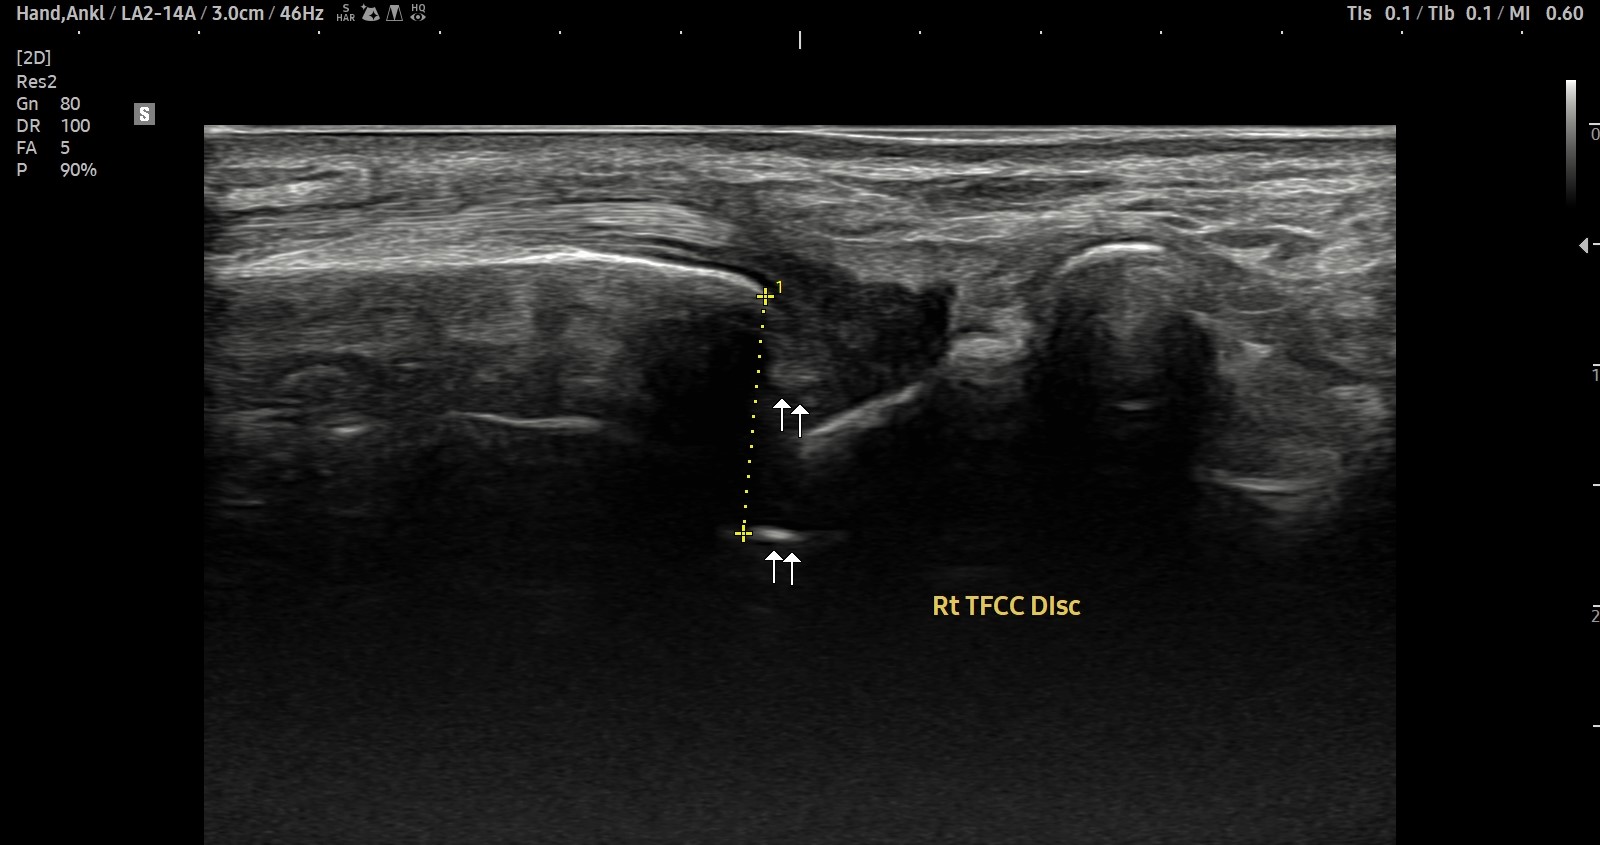

- 치료기간 : 25 .5 30 . ~ 25 . 6 .27

- 치료횟수 : 5 회(dna 1cycle)

양 손목 신근지대 건초염 & 건염

치료 전

치료 후